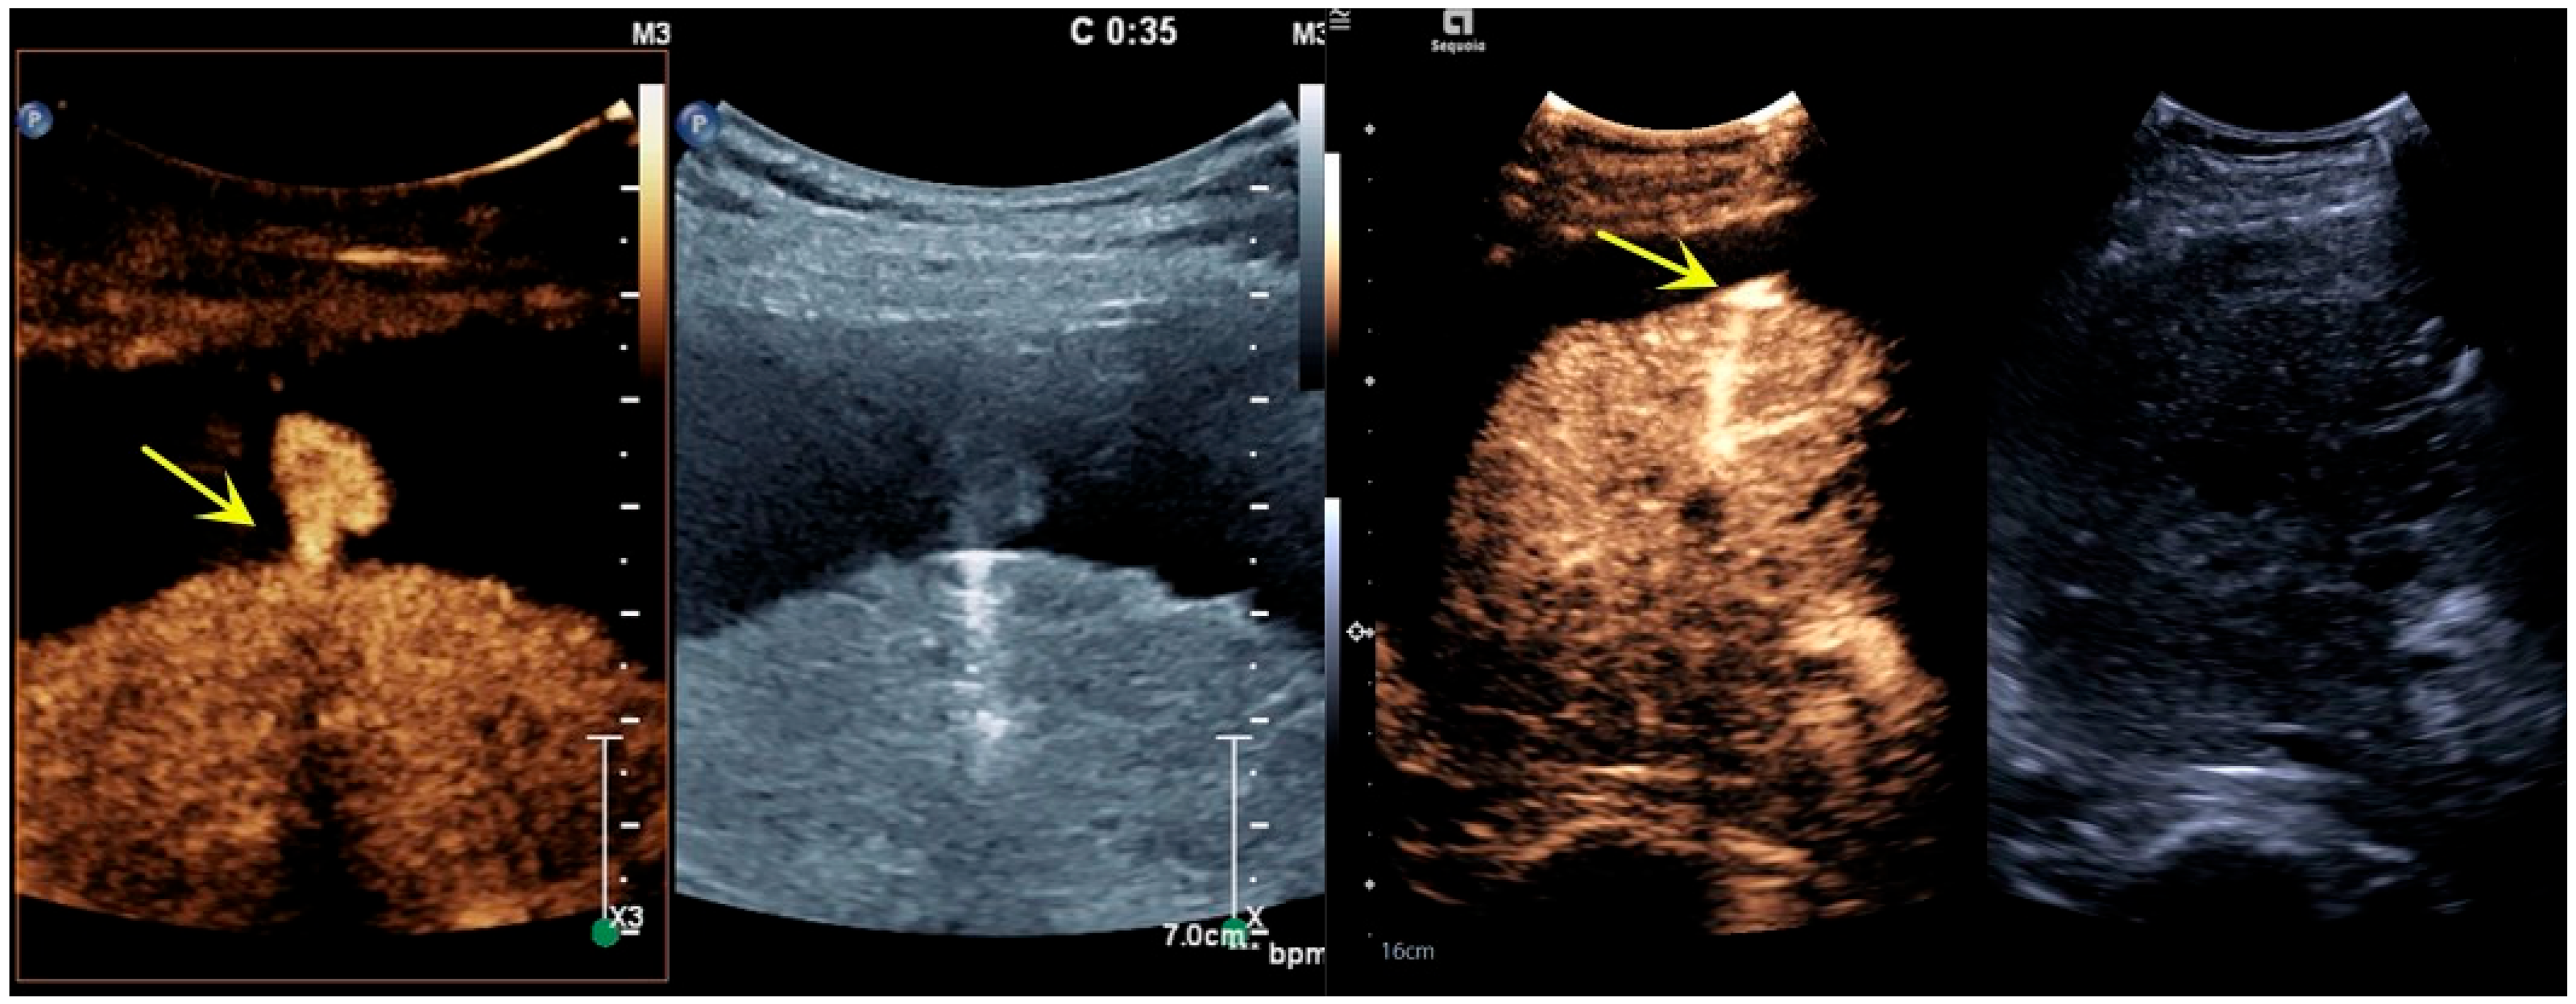

3.1. Imaging Features